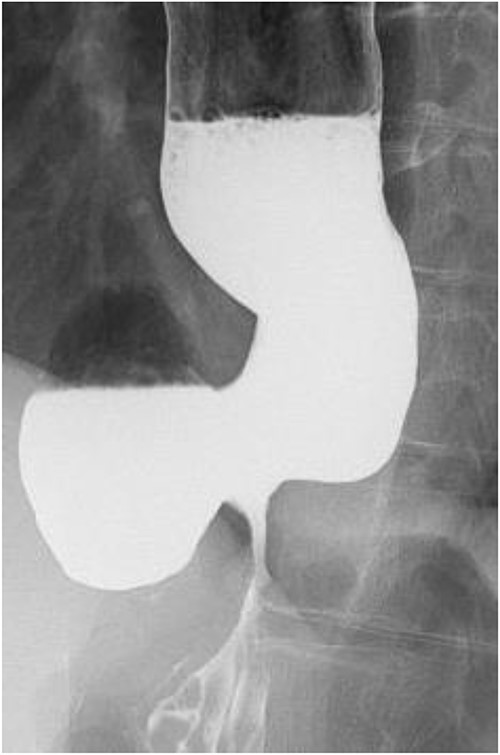

A 60-year-old female with dysphagia and vomiting visited the university hospital. In 2007, she underwent esophageal diverticulum resection (procedure unknown) with a diagnosis of an esophageal diverticulum, which subsequently recurred. In 2011, she underwent a transesophageal hiatus diverticulectomy and a fundoplication (Nissen procedure) at a local hospital. In 2013, dysphagia and vomiting appeared. The patient was diagnosed with recurrence and underwent balloon dilatation for follow-up. In 2015, the patient came to our hospital due to persistent symptoms. After one balloon dilation, the patient did not show any improvement and was referred for surgery. Esophageal fluoroscopy revealed a diverticulum 5 cm in size in the lower esophagus just above the eruption. There was no significant change in the diverticulum size before and after dilation (Figs 1 and 2). Gastrointestinal endoscopy revealed a diverticulum in the lower esophagus, with a residue accumulation (Fig. 3). The esophagus directly below the diverticulum was narrowed. The patient was diagnosed with recurrent lower esophageal diverticulum and underwent surgery.

Esophageal fluoroscopy (before dilation). There was a 5 cm-sized diverticulum in the lower esophagus just above the eruption.